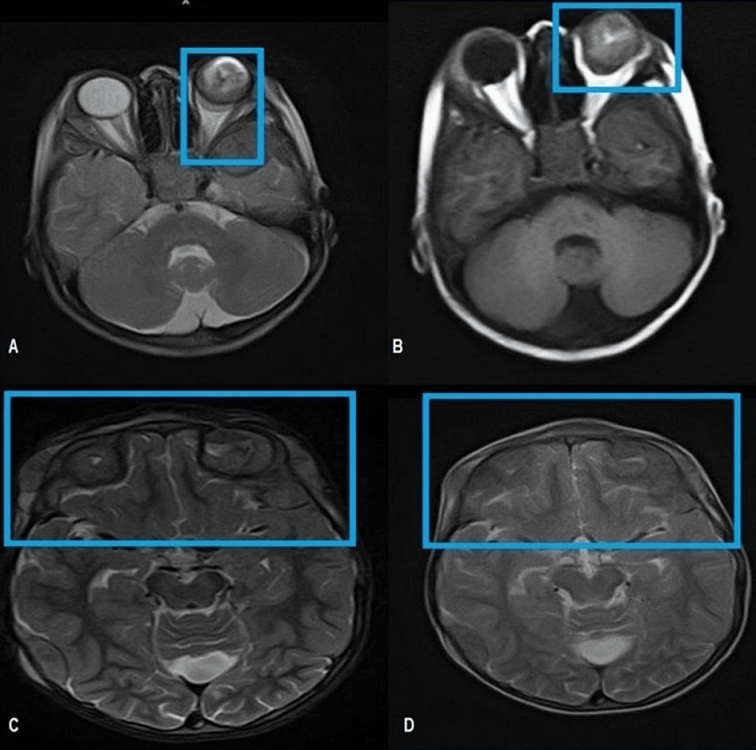

Magnetic resonance imaging (MRI) of the brain and orbit showed an intraocular retro-globular mass with retinal detachment and orbital hemorrhage. There were multifocal scalp-based lesions with an enhancing extradural soft tissue component along the left greater wing of the sphenoid, bi-frontal, and left parietal regions, causing bulges and mild leptomeningeal enhancement (Figure 2 [Fig. 2] and Figure 3 [Fig. 3]).

Figure 2: Enlarged left orbit showing intraocular retro globular mass with retinal detachment and T1W bright signal suggesting internal hemorrhage. A: T2W Axial MRI brain reveals an intraocular mass in the posterior aspect of the left globe abutting the retina returning heterogeneous hypointense signals. B: T1W axial MRI brain shows an intraocular lesion with a V-shaped T1W hyperintense signal in the posterior left globe reflecting hemorrhagic retinal detachment. Note the extraocular extension of the tumor through the sclera resulting in the deformed globe. C and D: Axial MRI T2W images cranial section reveals extra-axial low signal intensity masses in the bi-frontal region and left scalp.